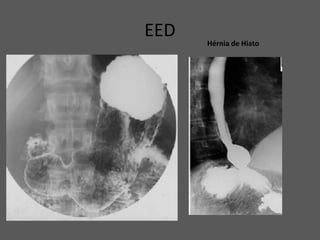

EED Hérnia de Hiato